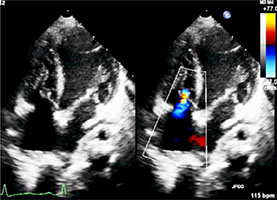

9、日齢15の新生児。呼吸障害と経皮的酸素飽和度の軽度低下を認め3日前から増悪した。心エコー図を示す。この症例で誤っているのはどれか。2つ選べ。

- 心拡大をきたす。

- 下大静脈が拡大する。

- 垂直静脈が下行している。

- 心房間交通は左右短絡である。

- 四腔断面像は新生児遷延性肺高血圧症と類似する。

正解:a, d